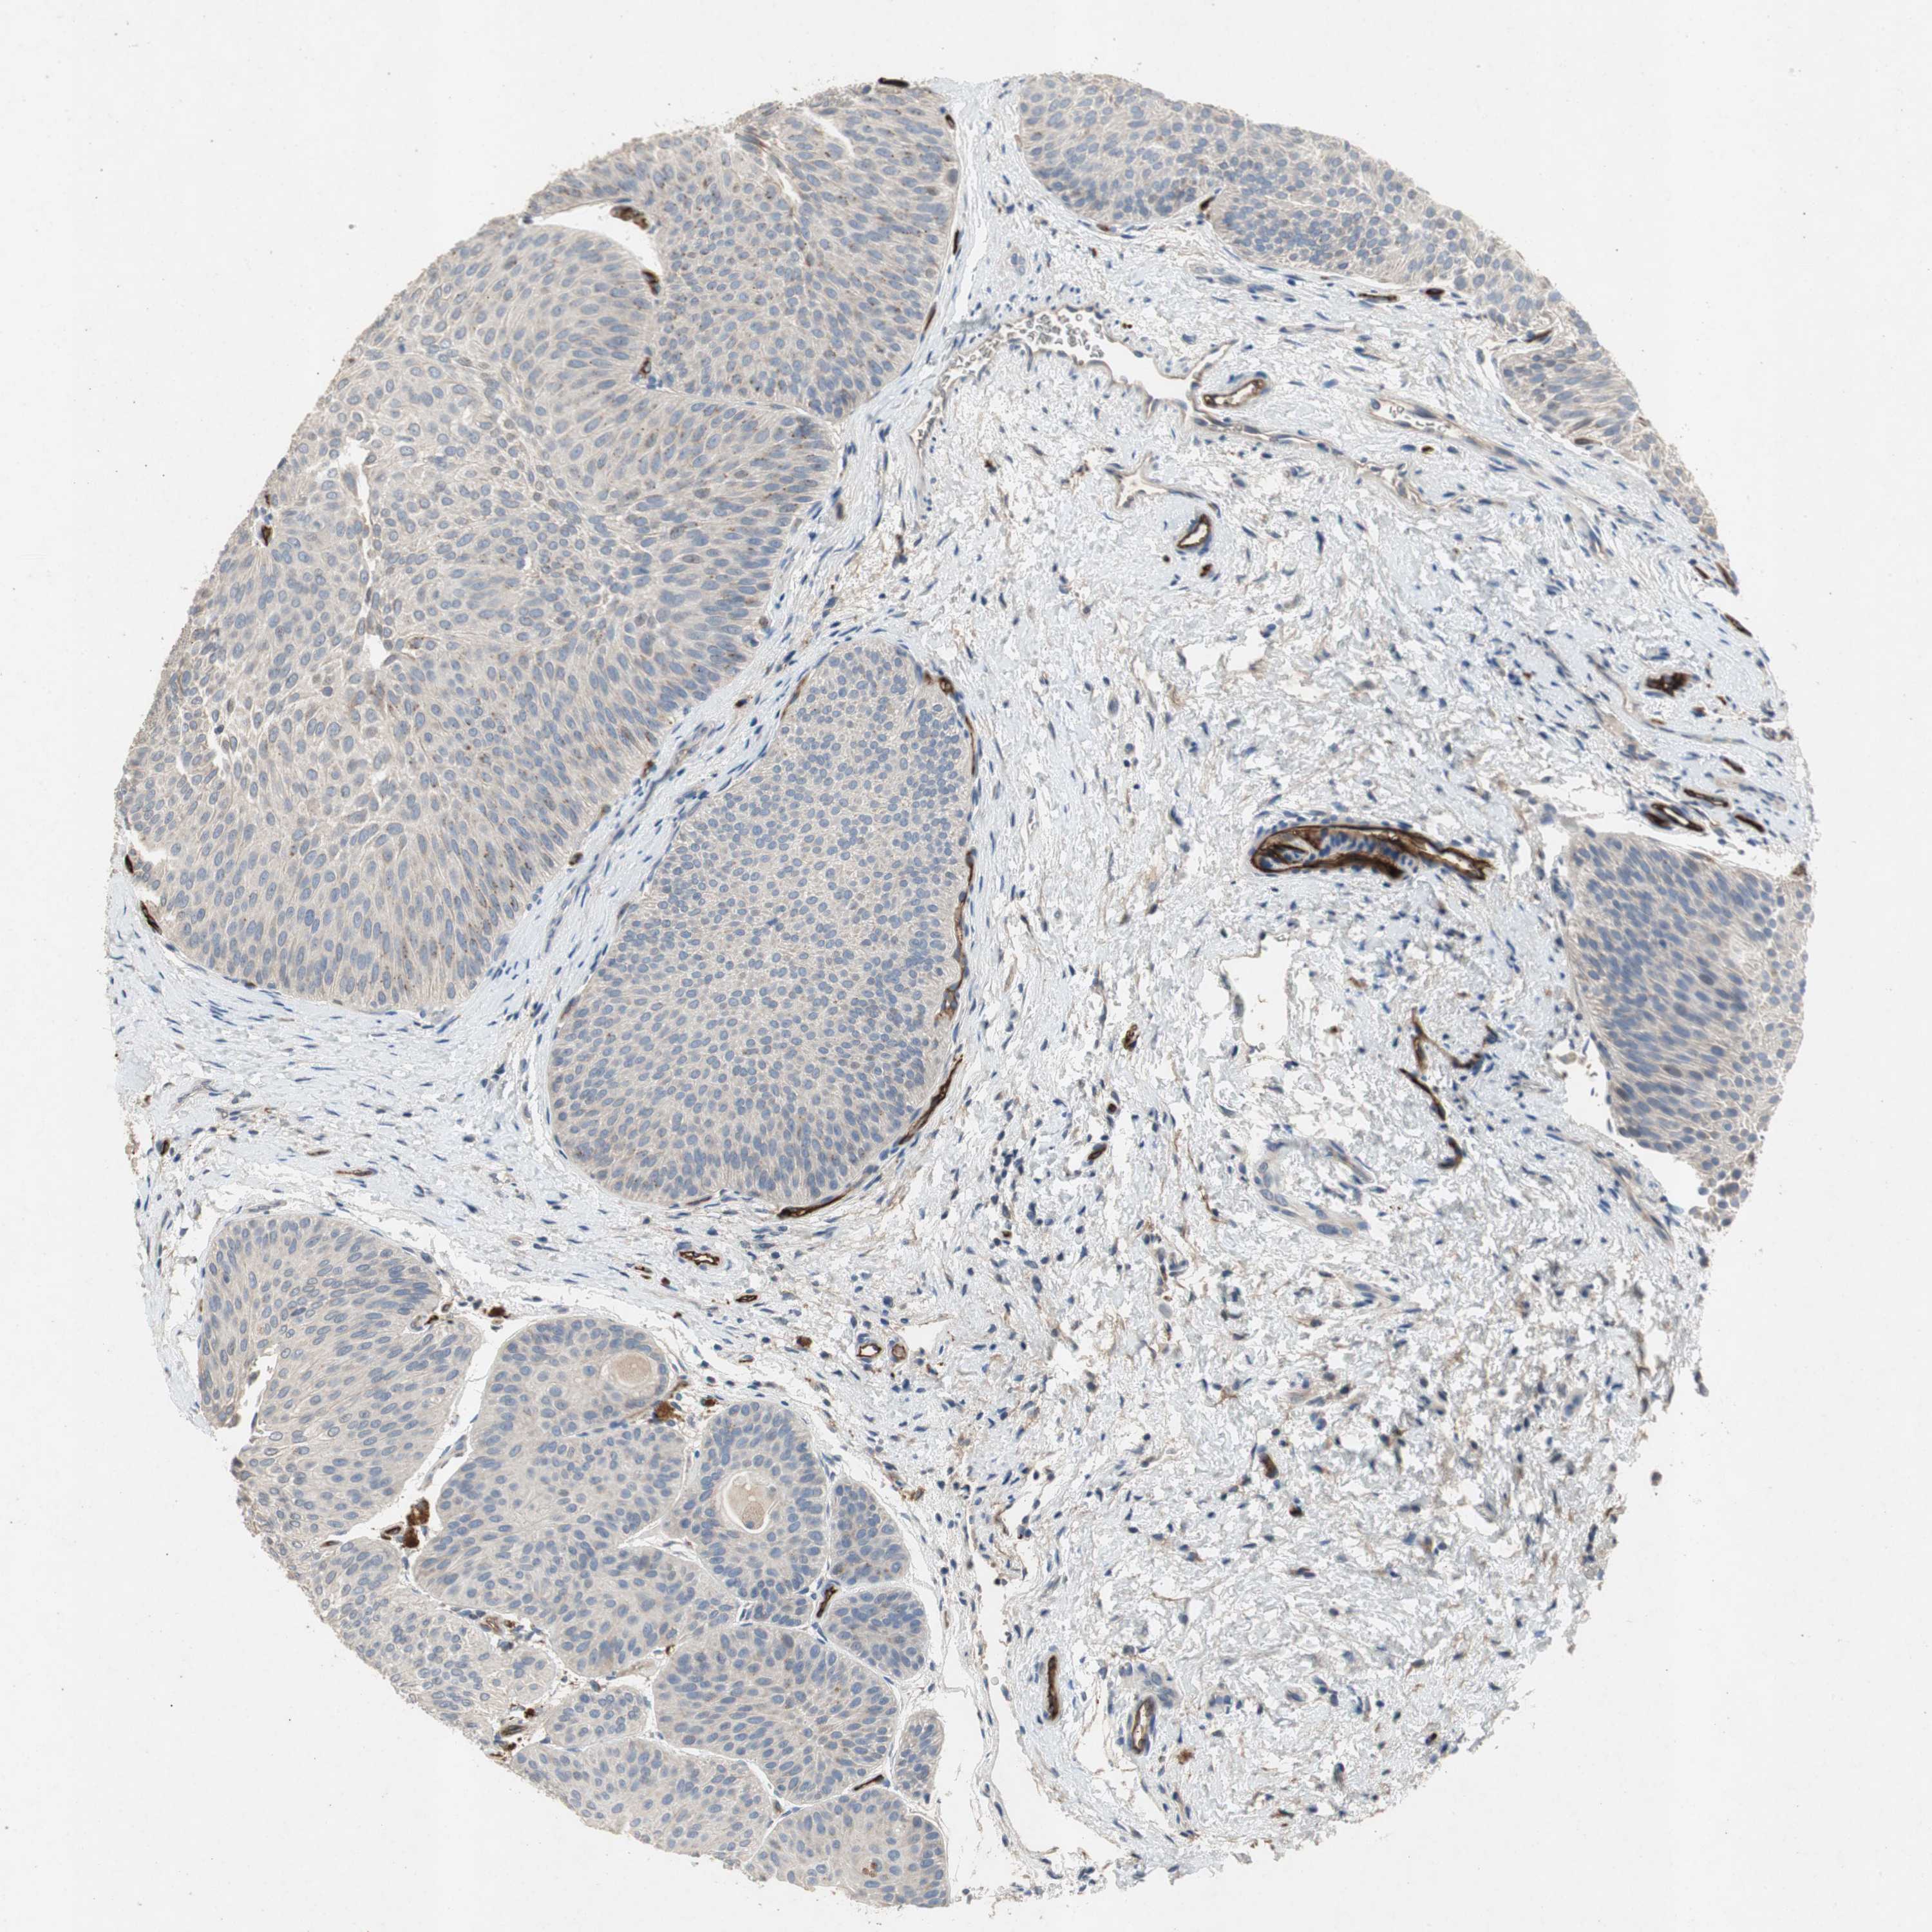

UROTHELIAL CANCER - Protein expressioni

A mouse-over function shows sample information and annotation data. Click on an image to view it in a full screen mode. Samples can be filtered based on level of antibody staining by selecting one or several of the following categories: high, medium, low and not detected. The assay and annotation is described here.

Note that samples used for immunohistochemistry by the Human Protein Atlas do not correspond to samples in the TCGA dataset.

Antibody stainingi

Antibody staining in the annotated cell types in the current human tissue is reported as not detected, low, medium, or high, based on conventional immunohistochemistry profiling in selected tissues. This score is based on the combination of the staining intensity and fraction of stained cells.

Each image is clickable and will lead to virtual microscopy that enables deeper exploration of all samples and also displays staining intensity scores, fraction scores and subcellular localization as well as patient and tissue information for each sample.

Antibody HPA007105

Antibody HPA008765

Antibody CAB020829

Staining

High

Medium

Low

Not detected

Intensity

Strong

Moderate

Weak

Negative

Quantity

>75%

75%-25%

<25%

None

Location

Nuclear

Cytoplasmic/membranous

Cytoplasmic/membranous,nuclear

Urothelial carcinoma, Low grade

Urothelial carcinoma, High grade